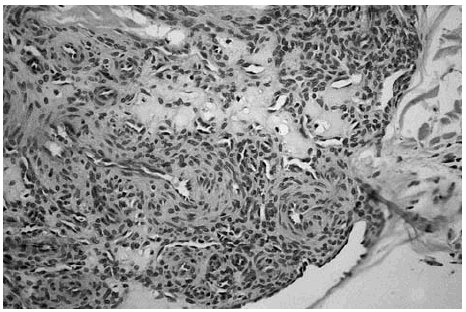

Las áreas hipocelulares presentaban un estroma escleroso. Las células que contenían se disponían en haces no muy bien estructurados. Estas células mostraban un núcleo alargado con extremos redondeados que recordaban fibras musculares lisas (fig. 4).

Fig. 4.--Detalle de una transición entre una zona hipocelular con células fusiformes dispuestas en haces no muy bien estructurados con un estroma hialinizado y una zona hipercelular.